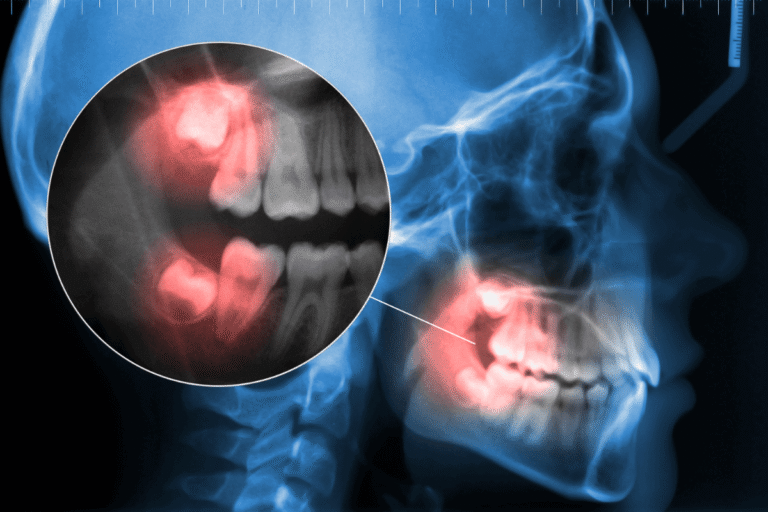

Мъдреците – известни още като третите молари – са последните зъби, които израстват. Обикновено те пробиват венеца между 17 и 25 годишна възраст. Често мъдреците не изникват в съответствие с останалите зъби, заклещват се частично или напълно във венеца или челюстната кост. Това състояние се нарича ретиниран мъдрец и често причинява проблеми за оралното здраве, като caries, заболявания на венците и инфекция.

Мъдрецът става ретиниран, когато в челюстта няма достатъчно място за правила подредба на всички зъби!

Видове ретинирани мъдреци

Съществуват 4 вида ретинирани мъдреци, всеки съответстващ на специфичното разположение на зъба:

Мезиално ретиниран мъдрец – най-често срещания тип. При него мъдрецът се накланя напред (мезиално) към предната част на устата, често притискайки втория молар пред него.

Дистално ретиниран зъб – най-редкият тип. При него мъдрецът е е под ъгъл към задната част на устата.

Вертикално ретиниран мъдрец – мъдрецът се намира в правилна позиция за излизане, но все още се намира под венеца.

Хоризонтално ретиниран зъб – мъдрецът лежи изцяло настрани, заклещен под венеца. Често са много болезнени, тъй като оказват прекомерен натиск върху зъбите пред тях.